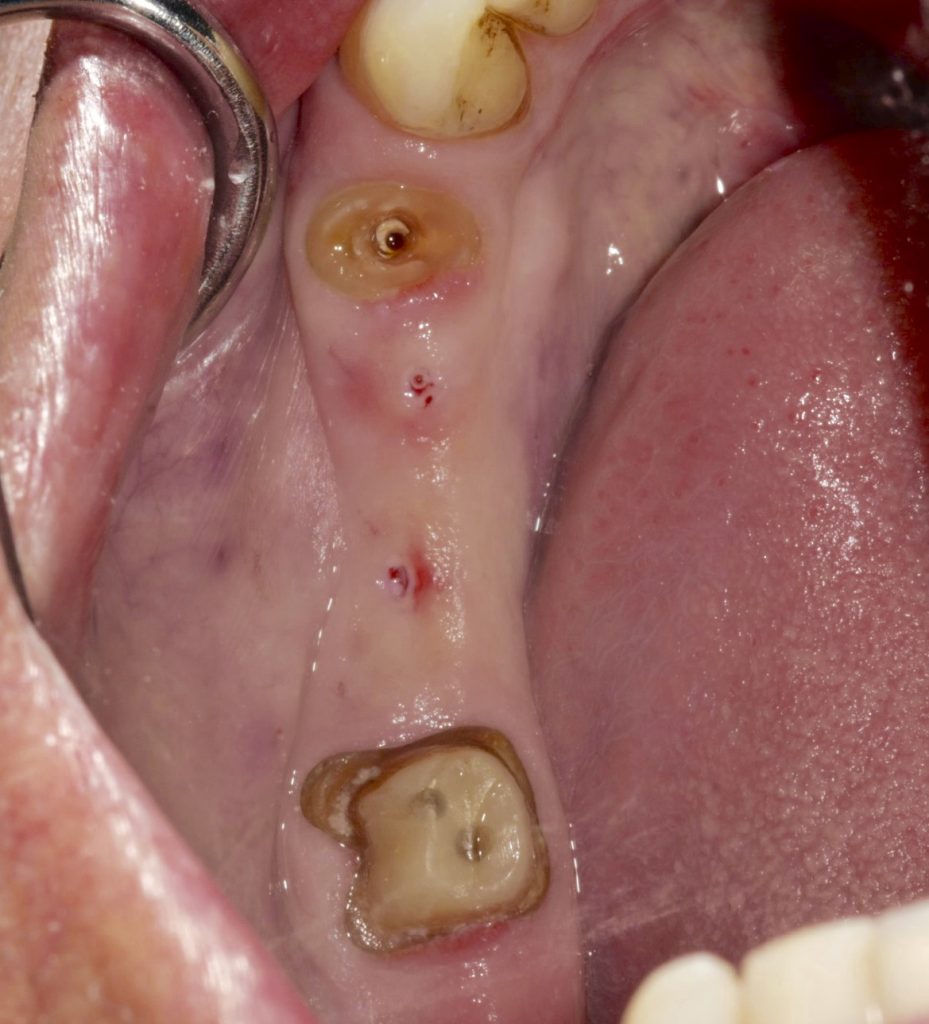

Autores: PRÓLOGO Asimismo, desde el punto de vista pedagógico, el profesional nobel en la materia tiene a su alcance la posibilidad de corregir cualquier posición implantaría en el ordenador, planear los provisionales y plasmarlos en la bio réplica antes de tocar al paciente a operar. Todos estos razonamientos nos llevan a presentar un caso de condiciones muy favorables para poner en práctica estos métodos como primer acercamiento a una Odontología Digital de alta calidad, con medios informáticos, que ya están presentes en la profesión de hoy en día, y será la protagonista única del futuro. Por otro lado, después de numerosos estudios que nos llevan a plantear el “gap” entre implante y pilar(abuttment), como principal responsable de la periimplantitis dado que la microbiota presente en el mismo es imposible de limpiar y en su presencia la cortical ósea reacciona reabsorbiéndose, nos ha llevado a utilizar implantes monobloc ya que los ejes implantarios y protéticos coincidían, y nos permitían su uso. Además, el circonio, ha mostrado a la luz de estudios muy recientes, una preservación y adhesión de los tejidos blandos superiores al titanio, tanto en su tratamiento de superficie de la rosca como a nivel gingival. DESARROLLO Paciente varón de 68 años, con antecedentes de radio/quimioterapia cinco años antes, con Rehabilitación Oral de los cuatro cuadrantes, con una Oclusión Mutuamente Compartida conservada, (REF.8) la que fracasa en el cuadrante 4, 19 años después. El mismo presentaba un puente de porcelana sobre circonio con pilares en 44 y 47, reemplazando el edentulismo de 45 y 46. Se produce la fractura del PM del 44, y ante una endodoncia antigua y corta, se decide implantar las zonas edéntulas, conservando temporariamente los pilares, hasta producida la oseointegración, para entonces también exodonciar el 44. DIAGNÓSTICO Tomamos impresiones del maxilar antagonista, Arco Facial Estático y realizamos montaje del mismo mediante la sistemática ARTEX. Producimos la relajación del músculo Pterigoideo Externo, para obtener la ORC (Oclusión en Relación Céntrica) mediante el método de Laminillas de Long, basado en el concepto de INERVACIÓN RECÍPROCA. Esto nos permitirá montar el maxilar inferior, tanto en su forma de: La primera para practicar la cirugía guiada y comprobar su eficacia, y el modelo de yeso para ser escaneado y confeccionar la GUÍA QUIRÚRGICA. La Biorréplica la obtenemos transformando los archivos DICOM que nos da el CBCT en archivos STL, y a partir de ellos, mediante una tecnología de PROTOTIPADO RÁPIDO, la obtención de un objeto físico en 3D a través de la aglutinación selectiva de una sucesión de capas de polvo. Procedemos a montar la biorrèplica y el modelo de yeso del caso. Podemos verificar la exactitud de las medidas del hueso residual en la bio réplica y compararlas con el scanner. Arrojando un resultado de 8,5 mm de cortical externa a cortical externa. Pudiendo también medir la distancia hasta el dentario. y comparar gracias a la ventana lateral de la biorréplica Dándonos 22mm de distancia. Con lo cual deducimos que implantes de 4,1mm por 12 mm serán perfectamente rodeados de hueso. Medimos también la distancia desde oclusal del antagonista, hasta el hueso desnudo. Lo mismo que, mediante la utilización de la guía radiológica, con un material radiolúcido colocado en gingival de la misma, podemos medir la altura de la encía. Con lo cual podemos calcular la altura del pilar. Es entonces cuando con el programa COC Diagnostix se realiza la programación final: Obteniendo no solo la ubicación, largo, ancho y ángulo de los implantes sino también los provisionales mediante CAD CAM. Ya entonces podemos hacer la práctica quirúrgica en la bio réplica, mediante la guía quirúrgica, instalando los implantes de prueba que no serán los de circonio, ya que la casa no cuenta con ellos, pero si otros de las mismas dimensiones. TRATAMIENTO Entramos ya en la cirugía propiamente dicha. Antisepsia de la zona a operar y zonas anexas. Comprobación del perfecto ajuste e inmovilidad de la G.Q. en boca durante la cirugía. Marcado de la encía y perforación de la cortical. Visión a través de la Guía de la mínima intervención anterior. Comprobación sin Guía. Incisión mínima mesio distal, para apartar y conservar encía queratinizada. Secuencia de drills, perforando a profundidad requerida Observación del Mínimo Trauma Implantes Strauman de Zirconio Monoblock en blíster y montádo en contrángulo reductor. Instalación controlando torque con contrángulo reductor. Comprobación clínica. Comprobación Radiográfica y con Guía. Toma de impresiones, y armado de modelos con técnicas de pasividad protética. Montaje. Resultado de las provisionales ejecutadas por CAD CAM Al no estar conformes con el resultado decidimos desechar dichas provisorias y optar por repetirlas. Nuevas provisorias realizadas mediante encerado convencional. Estado de los tejidos blandos. Provisorias en boca. Oclusión de Estímulo Inmediato. Ref.10: Carga inmediata .Alberto y Diego Bechelli. Comprobación mediante CBCT post operatorio Componentes del equipo (En la próxima presentación, mostraremos las coronas definitivas de porcelana sobre circonio, y la desoclusión provocada por una OCLUSIÓN MUTUAMENTE COMPARTIDA, sobre estos implantes y otros seis mas) REFERENCIAS

FIG:55

FIG:56

FIG:57

FIG:58

FIG:59-60-61-62

Fig. 59

Fig. 60

Fig. 61

Fig. 62

FIG:63

FIG:64-65

FIG.66-67

FIG:68-69

FIG.70-71